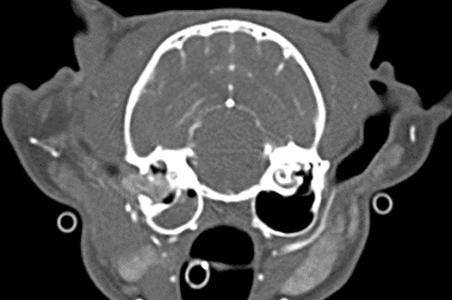

CT 검사를 통해 일반적인 방사선 상에서 확인할 수 없는 3차원적인 volumetric image를 구현하여 mm 단위의 작은 병변에 대한 감별과 정교한 3D 영상을 통해 선천적인 장기 또는 혈관 기형, 종양 및 전이 평가, 근골격계 질환, 비강/두개골 질환 등 다양한 질환의 진단에 사용될 수 있습니다.

두부 CT

두개 골절, 중/내이염, 비강 내 염증 및 종양, 안구 및 안와 내 병변, 갑상선 종양 등